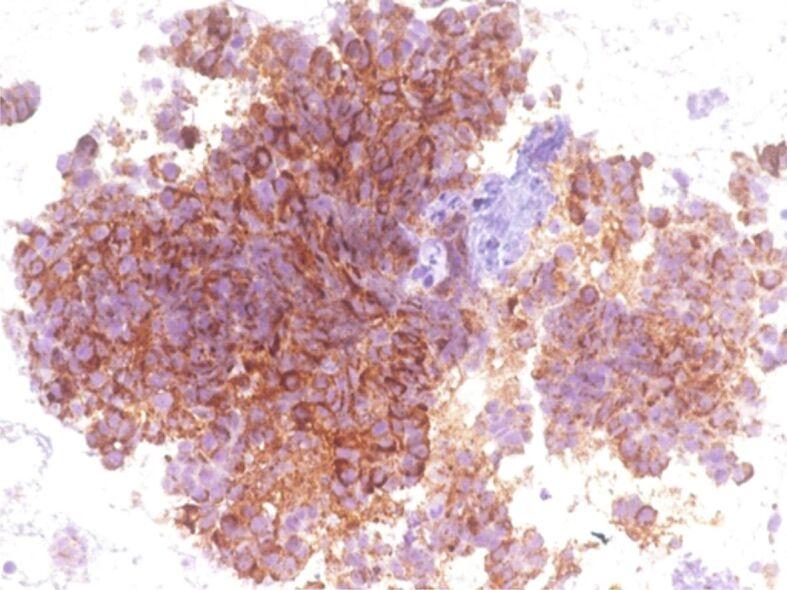

A total of 57 patients were ultimately selected to take part in our study. We performed immunohistochemical analysis based on the morphological diagnosis of the pancreatic tumors and assessed cytokeratin (CK)7, CK20, caudal type homeobox 2 (CDX2), MutL homolog 1 (MLH1), MutS homolog (MSH)2, MSH6, postmeiotic segregation 2 (PMS2) for all histopathologically uncertain pancreatic ductal adenocarcinoma (PDAC) and chromogranin A, synaptophysin, pan-CK AE1∕AE3 for pancreatic neuroendocrine tumors (pNETs). Cox hazard regression was performed to identify the factors influencing the survival rate. In univariate analysis, patient survival time was significantly associated with stage, location, surgical management and CK7 positivity. Our data show a statistically significant predictive relationship between stage (regional or metastatic) and hazard for survival (p=0.015). Tumoral location in the tail (p=0.015) and radicality surgery (p=0.015) significantly decrease the survival of pancreatic cancer (PAC) patients. The presence of CK7 (p=0.015) significantly increases the survival of pancreas cancer patients.

EUS-FNB has opened up a new path for pancreatic tumor diagnosis providing enough tissue for HP examination and IHC. A panel of several immunomarkers might aid in providing new therapies for PAC patients.